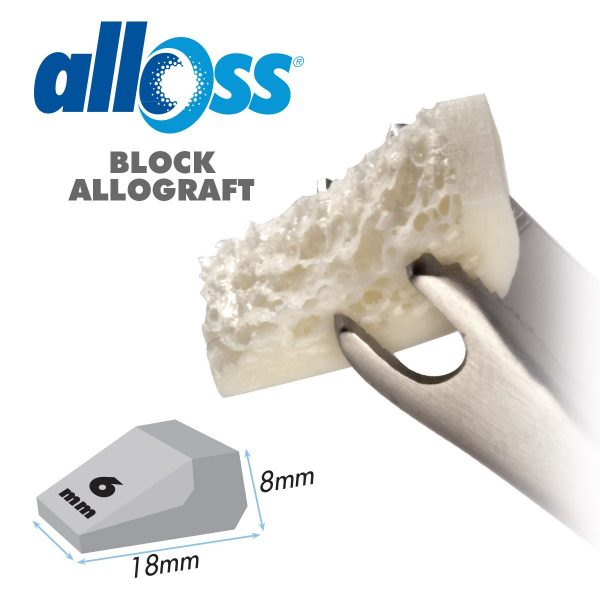

– Chứa thành phần từ xương vỏ để tăng độ cứng vững và thể tích. – Có chứa thành phần từ xương xốp để tăng độ lành thương và tăng sinh mạch máu. – Tốn ít thời gian chuẩn bị Chỉ định: – Khuyết hổng xương lớn (cần yếu tố nâng đỡ khung xương